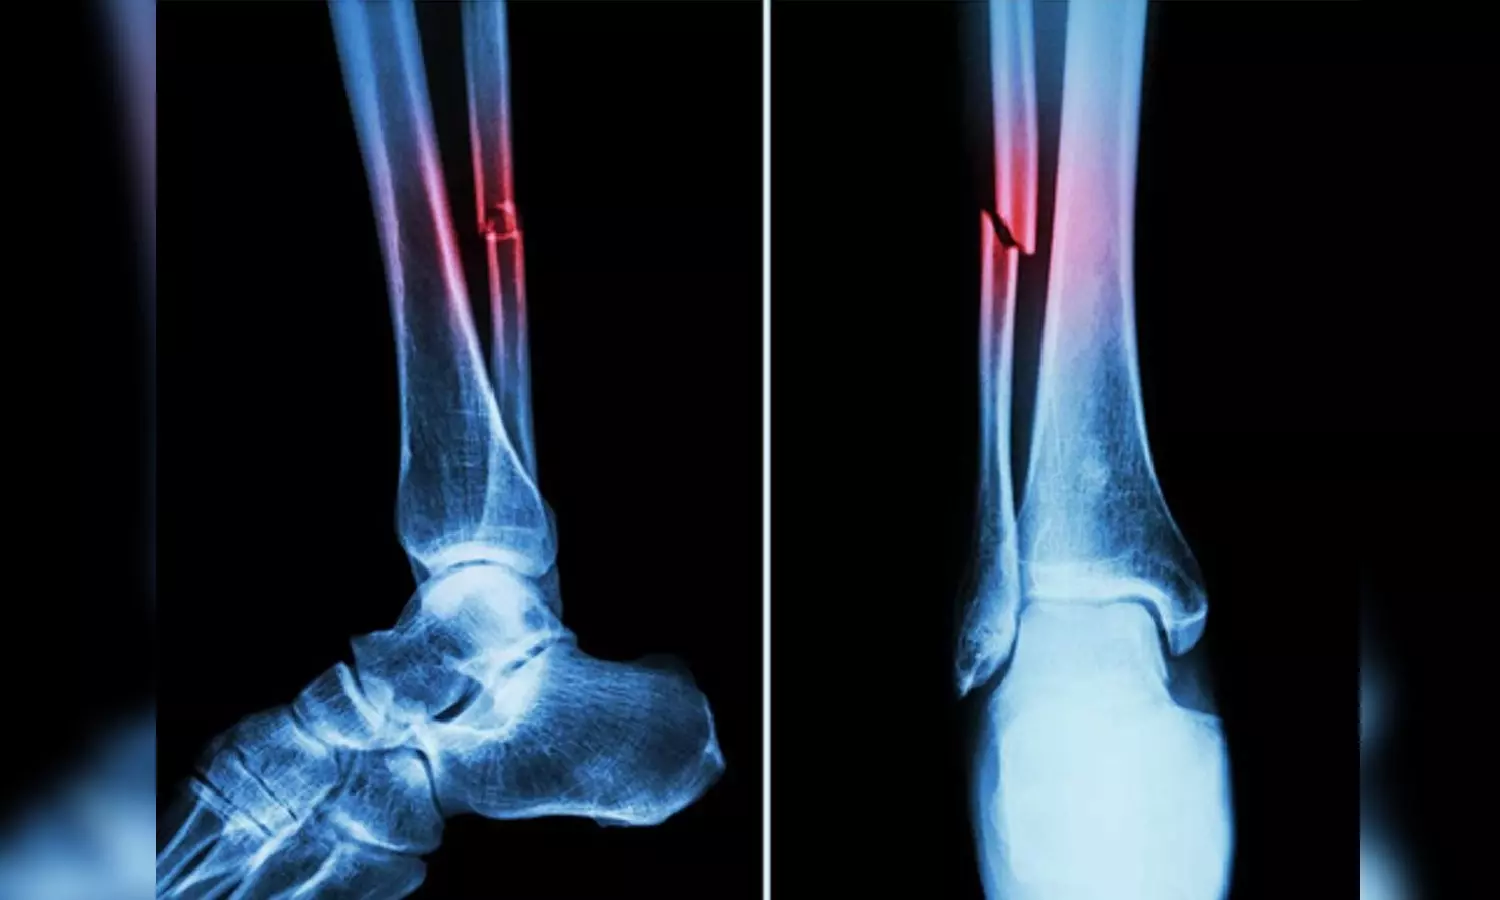

In the study, mice who had Covid-19 showed significant bone loss. This loss decreased the bone mechanical strength and increased the risk of fractures.

If similar bone loss occurs in human patients following their Covid‐19 recovery, it could leave them with a long‐term -- even permanent -- increased risk of fractures due to fragile bones. This is especially true in elderly patients.

The study suggested that the higher risk of fragility fractures, when a person falls from standing height or less, may be one of the underreported long-haul symptoms of Covid.

"This study has profound clinical implications," said R. Lor Randall, professor and chair of the Department of Orthopaedic Surgery. "Musculoskeletal ramifications of Covid may not be the first medical issue that comes to mind when one thinks about the pandemic. Nevertheless, many people suffer from fragile bones and Covid can put them at an even greater risk for fracture."